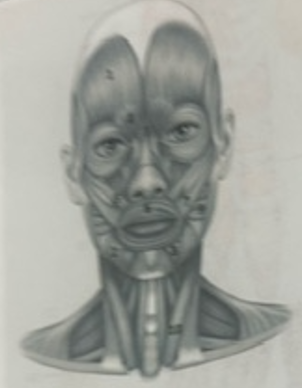

What muscle is 1?

Frontalis

What muscle is 2?

Depressor anguli oris

What muscle is 3?

Depressor labili inferioris

What muscle is 4?

Corrugator supercili

What muscle is 5?

Orbicularis oris

What muscle is 6?

Zygomaticus minor

What muscle is 7?

Zygomaticus major

What muscle is 9?

Buccinator

What muscle is 10?

Sternocleidmastoid

What muscle is 11?

Temporalis

What muscle is 12?

Masseter

What muscle is 13?

Risorius